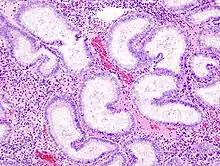

L'endomètre consiste en une couche simple d'épithélium cylindrique sur un tissu conjonctif, ce dernier étant aussi appelé stroma dans la littérature scientifique. L'épaisseur de ce tissu conjonctif évolue en fonction des niveaux d'hormones. A l'intérieur de l'utérus, des glandes cylindriques simples vont de la surface de l'endomètre jusqu'à la base du tissu conjonctif, qui acheminent aussi un apport sanguin depuis les artères spiralées utérines. Chez une personne avec un utérus et en âge de procréer, deux couches d'endomètre peuvent être distinguées. Ces deux couches sont présentes uniquement à l'intérieur de l'utérus, et non à l'intérieur des tubes utérins (anciennement appelés trompes de Fallope)[4],[5].

Adénocarcinome endométrioïde, vue d'une biopsie. Coloration HE.